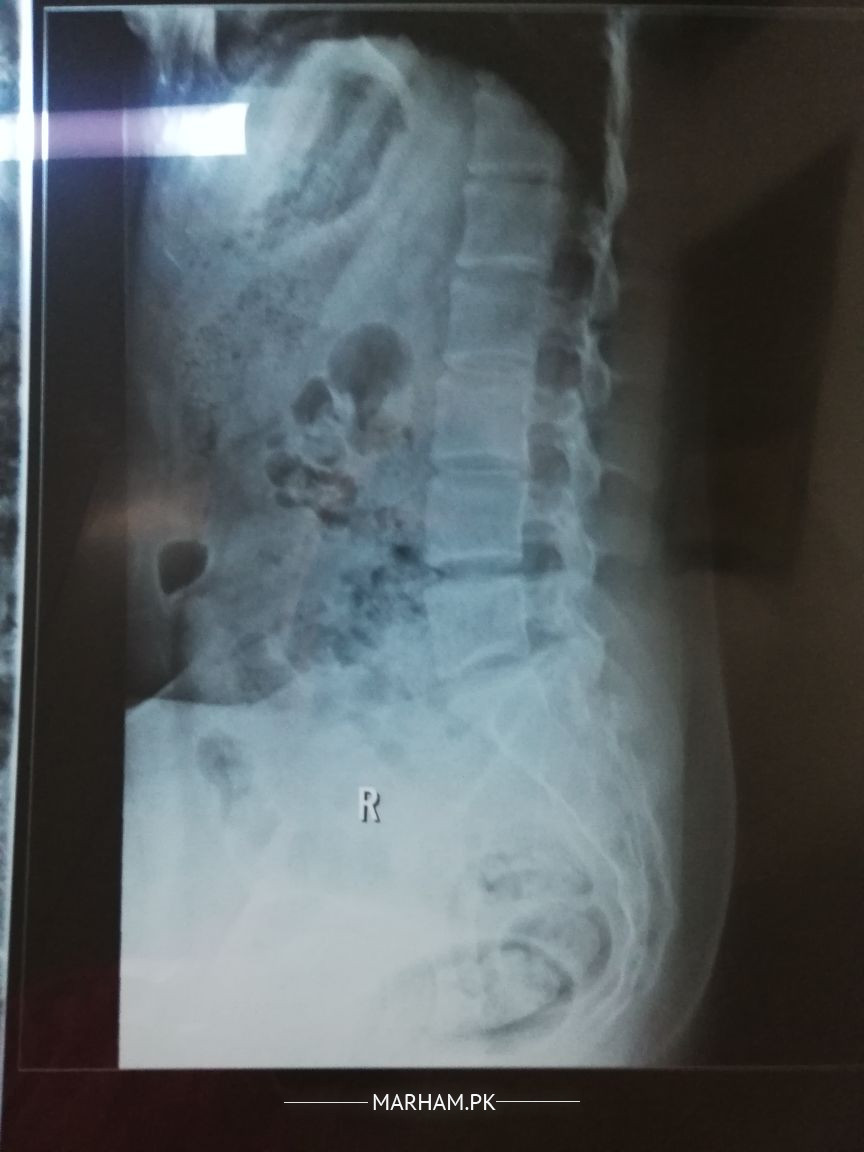

Asking For Self, Female 24, Islamabad

for approximately a wk, i was having discomfort lying supine, it was not pain but discomfort as i can feel my sacrum, a part of it bulging kind of. i thought its a misalignment. i feel slight back pain on long standing or sitting straight for a while for 2 days. is this lumbosacral spine xray normal?

Xrays seem to be fine . Many things have to be accounted for to get ro the bottom of the problem ... findling a solution on comments wont help much . I recommend getting an appointment

detailed history is required to find out the cause then it's treatment rest of these x rays seems ok . if u are interested then take appointment through Marham